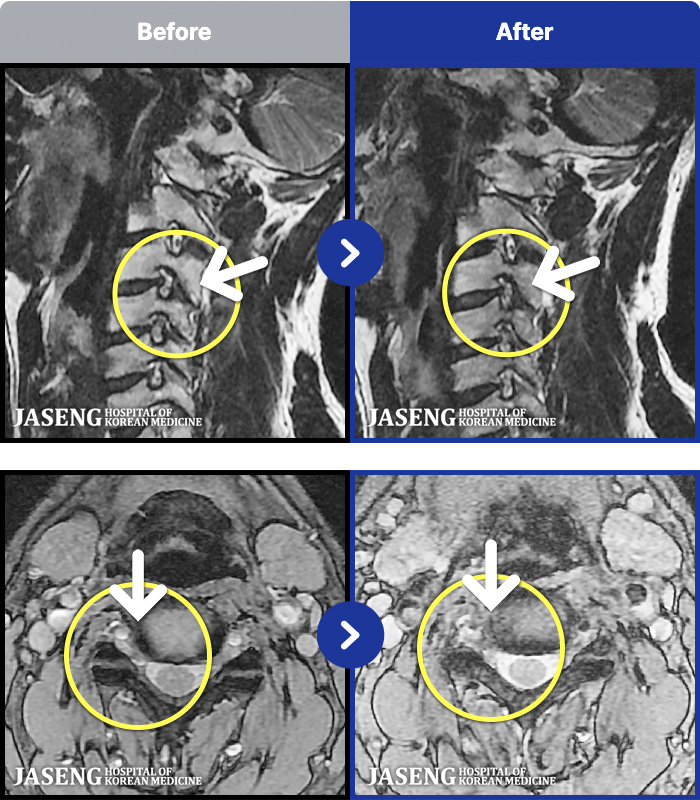

MRI ġ

MRI ũ ʸ Ȯϼ.

[Կñ:10.07.30~23.10.26]

[_㸮ũ] 㸮 ؽ

No.41

ȸ 270

2023.12.08